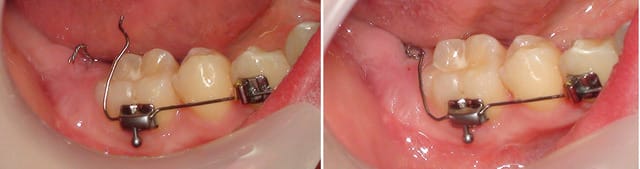

Le hasard a fait que je viens d'être confronté au même problème que Calou, sauf que la 47 étant très profonde (probablement ankylosée) il n'aurait pas été raisonnable d'exposer sa couronne et que son dégagement et le collage d'un bouton avec sa ligature ont été réalisés au cabinet.

Voici le système que j'ai mis en place. Le fil est un "TMA .016".

La hauteur de la muqueuse au niveau 47 ne permettait pas ici de faire comme le préconise notre ami. A-t-il, lui, des cas à nous montrer ?

Daniel

P.S. les photos datent d'hier.

Une ligature de traction peut se rabattre. les nombreuses pliures sur l’arc T.M.A. montrent la difficulté d’une mise en forme en bouche, même pour quelqu’un d’aussi expérimenté que Dancha

Ceci dit, notre ami Daniel ne nous a pas dit comment il obtenait un effet de traction axiale de la 47 avec un arc rond qui peut tourner dans le tube et Bk. de 46/44 (effet manivelle).

beau travail, on ne voit même plus de traces de cicatrice d’incision, la chirurgie de dégagement ne doit pas être récente, tu es sur que la dent est ankylosée ? Essaye avec un arc carré 16*x16*, immobilisé en rotation dans le tube de 46 et le Bk. de 44 par de la résine, peut être que ta dent va se désankyloser …